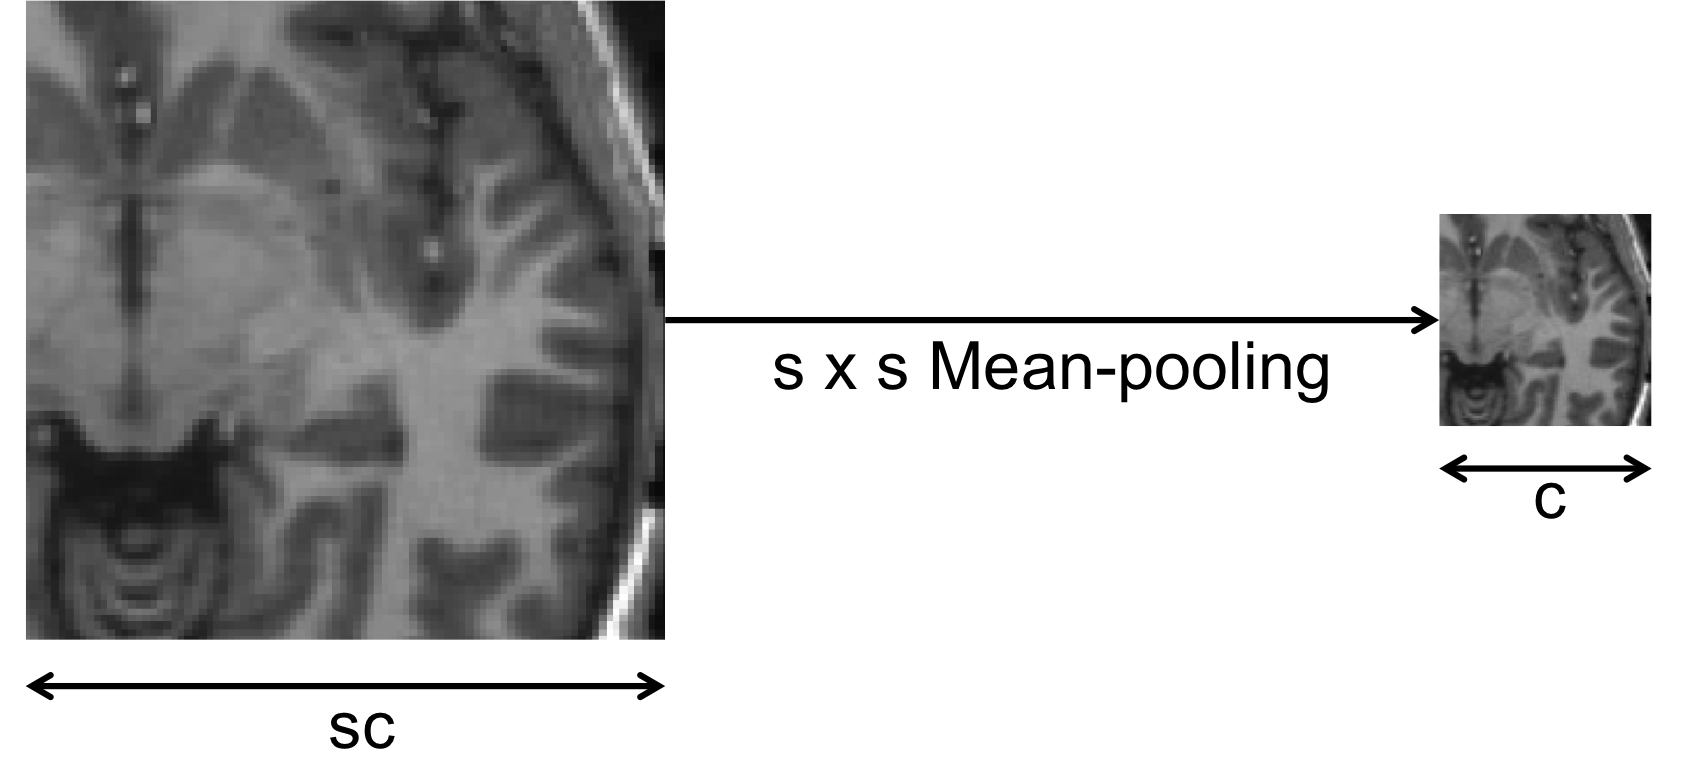

Refer to caption

Figure 2: A downscaled patch spans the same region of the MRI as the original patch but with a lower resolution.

A second set of inputs was designed to preserve global spatial consistency. Unlike unstructured segmentation tasks, in which different regions can be arbitrarily positioned in an image, anatomical regions consistently preserve the same relative positions in all the subjects. Including global information is therefore likely to yield additional improvements. An obvious strategy would be to simply increase the size of the 2D and/or 3D patches introduced earlier so as to span larger portions of the image and cover more distant anatomy. However this would generate very high-dimensional inputs requiring large memory for storage and would add computational complexity. Instead, we extract large 2D orthogonal patches that we downscale by a factor s𝑠s. As illustrated in figure 2, the downscale operation simply reduces the resolution of the patch by averaging voxel intensities within small square windows of size s×s𝑠𝑠s\times s. More precisely, if sc×sc𝑠𝑐𝑠𝑐sc\times sc is the size of the original full-resolution patches, then the downscaled patches have sizes c×c𝑐𝑐c\times c. In neural network terminology, this operation is equivalent to a s×s𝑠𝑠s\times s mean-pooling with stride s𝑠s. As a result, the downscaled patch still captures as large portions of the MRI as the original patch but with lower resolution.